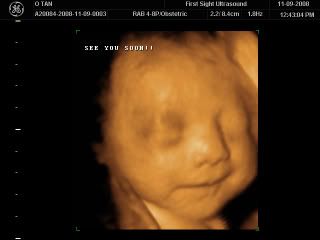

Finally Baby Caleb giving us a bye bye smile! Its so amazing, it was 24mins by the time he gave us this smile! It seems like he knows its time to say bye bye! Well we are gonna see him really really soon, just another 9 weeks or so... We'll see for sure who he looks like, his eyes, his lips, his ears... but for now, he definitely have his mummy's big big nose! And not forgetting that chubby little cheeks! So cute... We so wanna pinch his puffy cheeks.